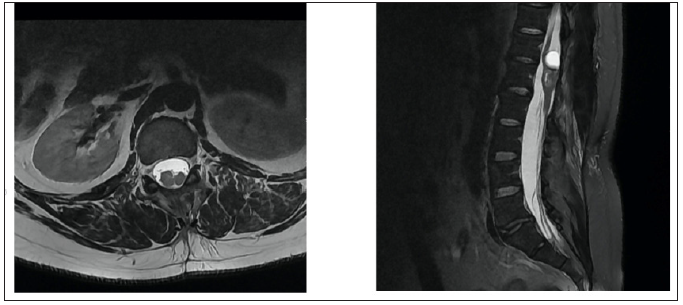

A 34-year-old male patient presented with a few months’ history of back pain. The patient had been treated with non-steroidal anti-inflammatory drugs (NSAIDs) for a few weeks in an outpatient clinic by a neurologist. Despite the treatment the back pain became constant and the patient started experiencing weakness in both legs while climbing stairs. The patient was referred for magnetic resonance imaging (MRI) of the thoracolumbar region (Figure 1 & 2). The MRI scan showed a multicompartmental heterogeneously enhanced intramedullary lesion located along Th12 and L1 vertebral bodies. A computed tomography angiography scan was also conducted and revealed neither spinal dysraphism, nor pathological vascular nidus. The patient was admitted to the Department of Neurosurgery in our hospital with spastic lower paraparesis (3 out of 5 on the muscle strength scale), bilateral positive Babinski sign, bilateral hypoesthesia below L1 dermatome, proprioceptive dysfunction in the lower extremities. Surgical treatment was suggested aiming for neural decompression, histologic verification and resection of the lesion. Laminectomies of Th12, L1 and partially on Th11 and L2 were conducted. Motor evoked potentials (MEPs) were monitored during the operation (Figure 3). The tumor was partially removed due to its adherence to the surrounding spinal cord and temporary deterioration of MEPs during surgical resection (Figure 4). The dura mater was closed with a watertight running suture and sealed with autologous fibrin glue. The histological examination revealed a mature teratoma (Figure 5). The patient had an uneventful postoperative period and was ambulating independently/muscle strength 5 out of 5/ on the 7th postoperative day. Control MRI was conducted 1 month postoperatively (Figure 6).

Figure 6: Post-operative axial reconstruction of T2-weighted MR-image of the spine at L1 vertebral body level and sagittal reconstruction Df T2-weighted MR-image of the spine.